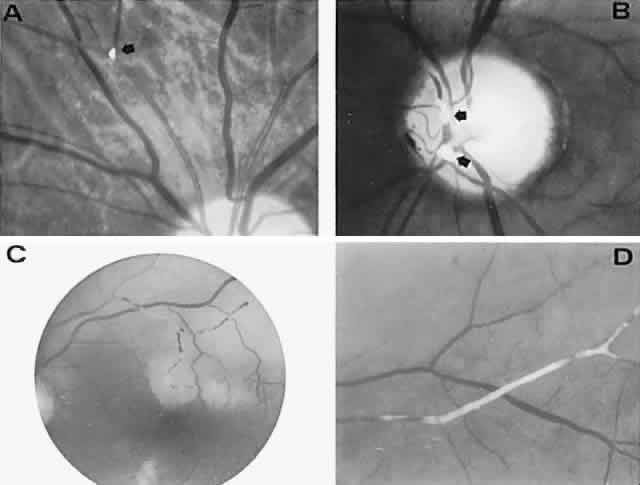

With acute infarction, the retina becomes opaque and takes on a creamy or gray appearance. Atheromatous material in the form of “bright plaques” of cholesterol or other microemboli may be seen, especially lodged at arterial bifurcations (Fig. 5). Segmental arteriolar mural opacification (see Fig. 5D) may follow retinal microembolization by weeks to months, and such sheathing may be as useful as the recognition of the cholesterol embolus itself.43 ERG may show diminished B-wave amplitude, a finding indicating inner retinal ischemia. Weeks following retinal infarction, the optic disc becomes pale, and the arterial tree becomes narrowed in the sector corresponding to the arterial occlusion.

Fig. 5. Retinal microembolic phenomena. A. Bright cholesterol plaque (arrow) impacted at an arterial bifurcation. Thin crystal does not obstruct flow. B. Cholesterol crystals in disc vessels (arrows). Often, the plaque appears larger than the vessel diameter. C. Infarcted opaque retina. The artery contains emboli (? fibrin platelets) that have obstructed flow. D. Reactive opacification of the arterial wall. Fluorescein angiography demonstrated flow through this formerly occluded vessel.